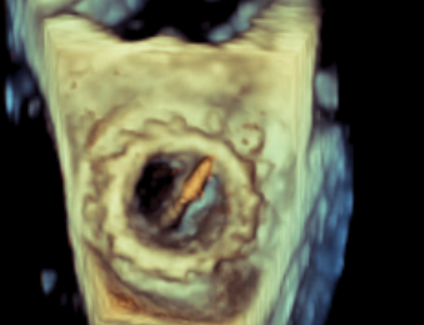

术中影像监护与评估(DSA&TEE)

收缩期未见瓣周漏

左房内未见对比剂显影